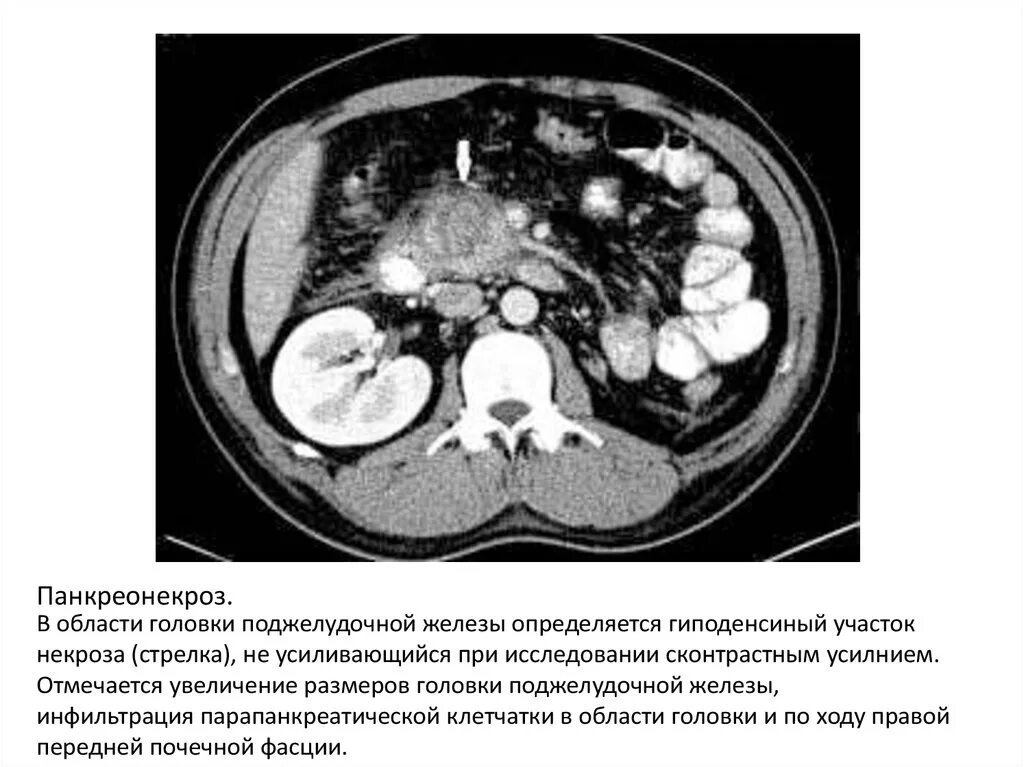

Инфильтрация паранефральной клетчатки на кт. параколитическая клетчатка кт. парапанкреатическая клетчатка инфильтрирована. перипанкреатический инфильтрат.Кт при остром панкреатите. парапанкреатическая клетчатка. кт диагностика панкреатита. острый отечный панкреатит кт.Парапанкреатическая клетчатка. поддиафрагмальное пространство. внебрюшинное поддиафрагмальное пространство. парапанкреатическая клетчатка инфильтрирована.Парапанкреатическая клетчатка что это значитКлетчатка анатомия. понятие о клетчатке в анатомии. основы клинической анатомии. клетчатка понятие.Парапанкреатическая клетчатка что это значитПарапанкреатическая клетчатка. парапанкреатическая клетчатка инфильтрирована. парапанкреатическая инфильтрация. парапанкреатическая клетчатка дифференцирована.Парапанкреатическая клетчатка что это значитПарапанкреатическая клетчатка что это значитХронический панкреатит на кт. парапанкреатическая клетчатка на кт. кт поджелудочной железы. поджелудочная железа на рентгенограмме.Парапанкреатическая клетчатка что это значитПарапанкреатическая клетчатка что это значитПарапанкреатический инфильтрат. парапанкреатическая клетчатка дифференцирована.Парапанкреатическая клетчатка что это значитПарапанкреатическая клетчатка что это значитПарапанкреатическая клетчатка поджелудочной железы. отек парапанкреатической клетчатки. парапанкреатическая инфильтрация. острый деструктивный панкреатит кт.Парапанкреатическая клетчатка что это значитПарапанкреатическая клетчатка что это значитПарапанкреатическая клетчатка что это значитПарапанкреатическая клетчатка что это значитПарапанкреатическая клетчатка что это значитПарапанкреатический инфильтрат. перипанкреатический инфильтрат. парапанкреатическая псевдокиста на кт.Парапанкреатическая клетчатка что это значитПарапанкреатическая клетчатка что это значитПарапанкреатическая клетчатка что это значитПарапанкреатическая клетчатка что это значитПарапанкреатическая клетчатка что это значитПарапанкреатическая клетчатка что это значитПарапанкреатическая клетчатка что это значитПарапанкреатическая клетчатка что это значитПарапанкреатическая клетчатка что это значитПарапанкреатическая клетчатка поджелудочной железы. перипанкреатический инфильтрат. осложнения острого панкреатита презентация. перипанкреатическая клетчатка.Парапанкреатическая клетчатка что это значитКисты и свищи поджелудочной железы. инфильтрация парапанкреатической клетчатки. истинные кисты поджелудочной железы классификация. парапанкреатическая клетчатка поджелудочной железы.Парапанкреатическая клетчатка что это значитПарапанкреатическая клетчатка что это значитПарапанкреатическая клетчатка что это значитПарапанкреатическая клетчатка что это значитПарапанкреатическая клетчатка что это значитПарапанкреатическая клетчатка что это значит